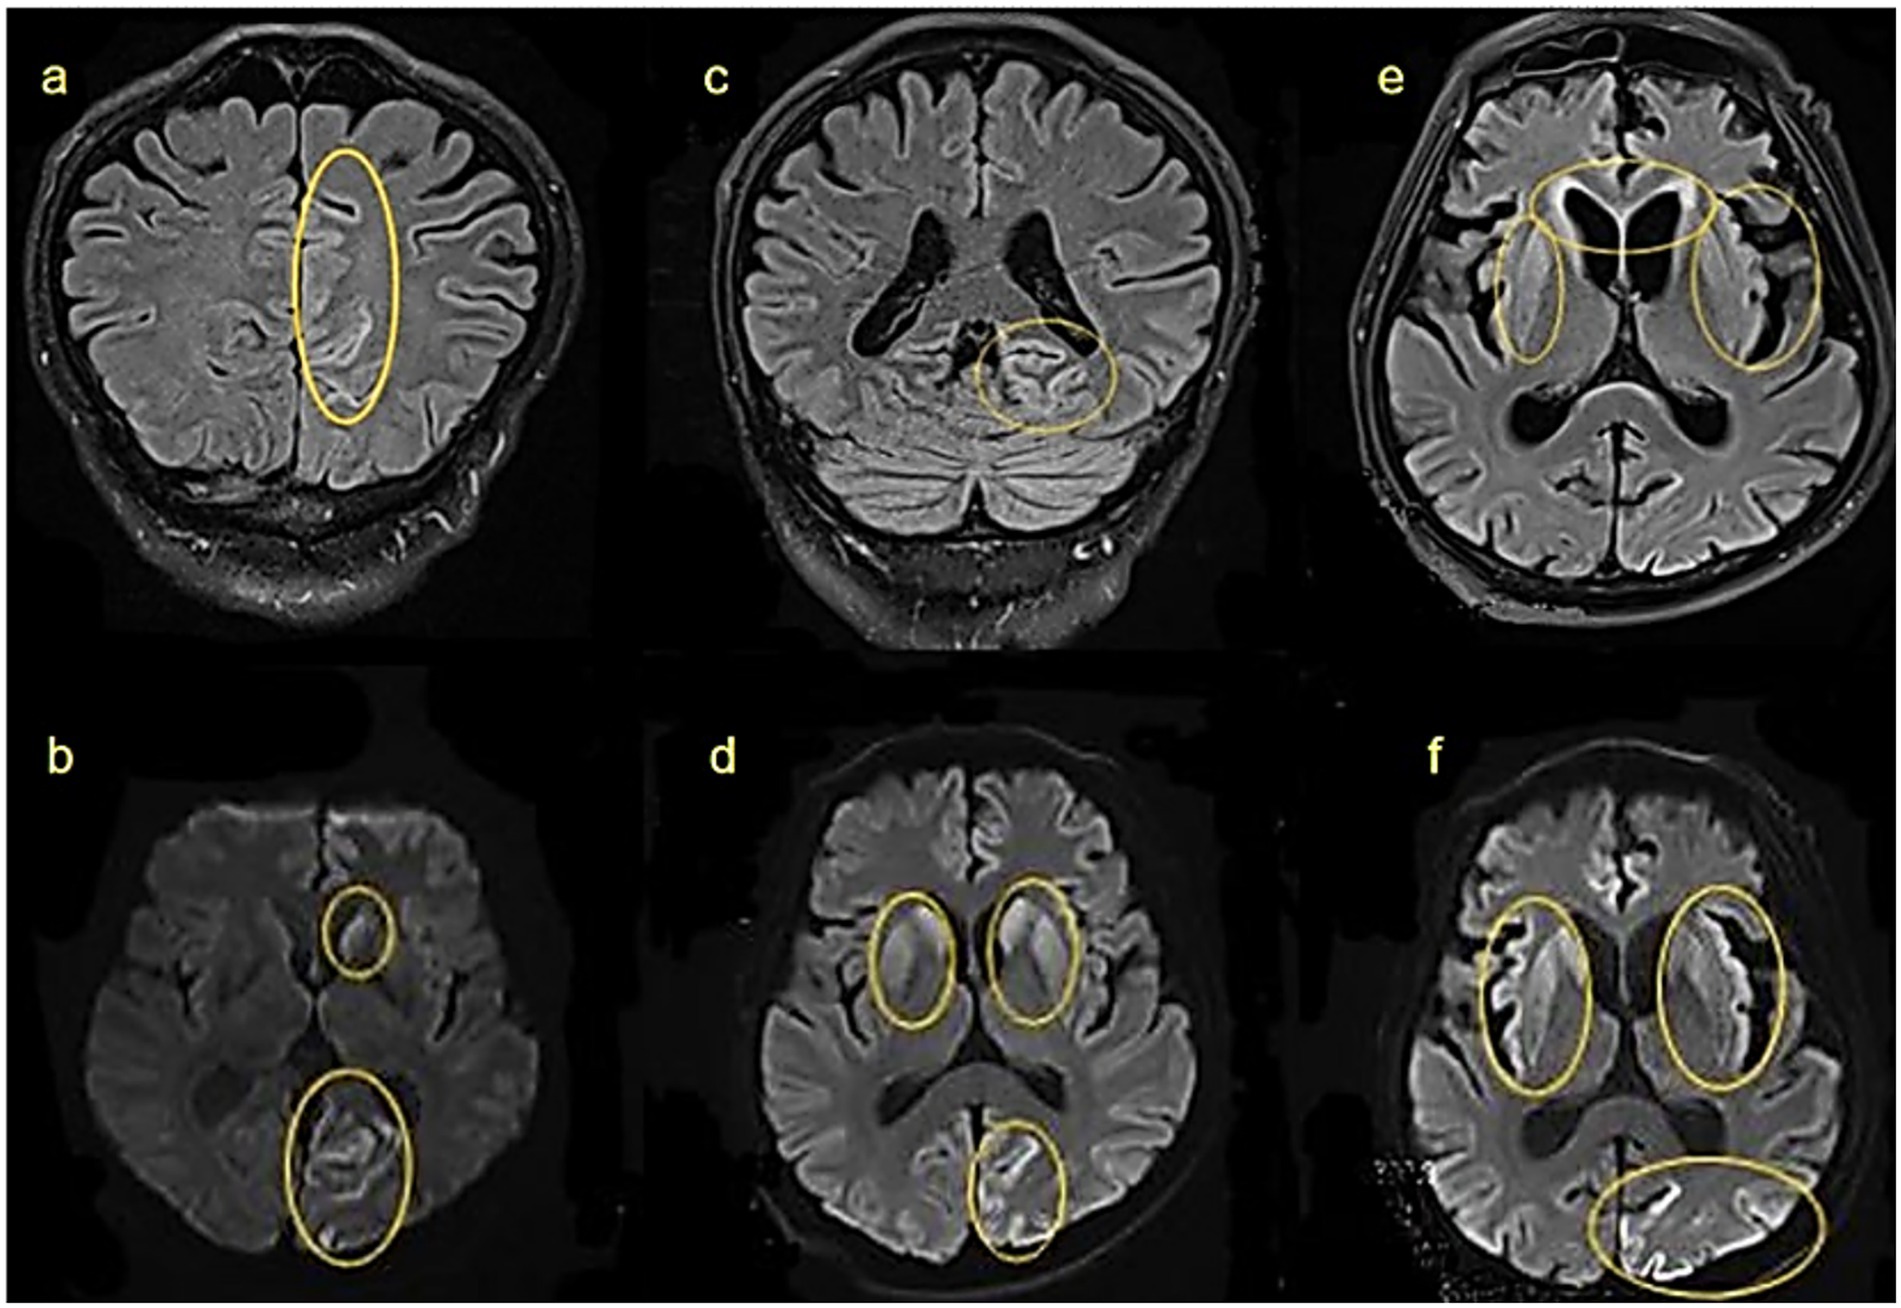

Six brain MRI scans labeled a to f, each with yellow outlines highlighting specific areas. Images a, c, and e show varying parts of the brain in axial sections. Images b, d, and f display different highlighted regions, suggesting areas of interest or abnormalities.

Figure 3. Cranial MRI findings at different stages of the same patient: (a,b) 8 weeks after onset: hyperintensities in the left caudate nucleus and left parieto-occipital cortex on FLAIR and DWI. (c,d) 12 weeks after onset: lesions extend bilaterally to caudate and lentiform nuclei. (e,f) 18 weeks after onset: further involvement of bilateral frontal lobes and insulae. Yellow circles highlight abnormal signals.

MRI findings correlated closely with this progression. By 8 weeks post-onset, FLAIR and DWI hyperintensities were observed in the left caudate nucleus and left occipitoparietal cortex (Figures 3a,b). By 12 weeks post-onset, as the disease progressed, abnormalities had spread to bilateral caudate nuclei, putamen, and the left occipitoparietal region (Figures 3c,d), at 18 weeks post-onset, further extension was seen into the bilateral caudate nuclei, lentiform nuclei, bilateral frontal lobes, insular lobes, and the left occipital-parietal cortex (Figures 3e,f). These changes may be related to further neuronal damage and the deposition of prion proteins.